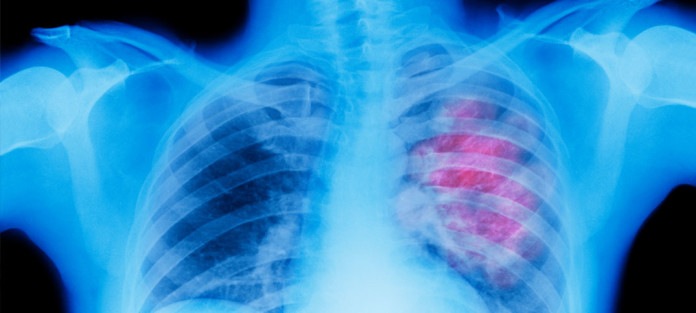

Científicos de Cancer Research UK han encontrado una combinación de fármacos que pueden desencadenar el proceso de autodestrucción de las células del cáncer de pulmón – allanando el camino para nuevos tratamientos, según un estudio que se presentará en el Instituto Nacional de Investigaciones Oncológicas (CNRI) Conferencia de Cáncer en Liverpool el próximo semana *.

El uso de células de cáncer de pulmón y los ratones los científicos mostraron que la combinación de dos fármacos, llamada TRAIL y un inhibidor de CDK9 **, alteraron los interruptores moleculares en el proceso de suicidio celular – obligando a las células cancerosas a autodestruirse.